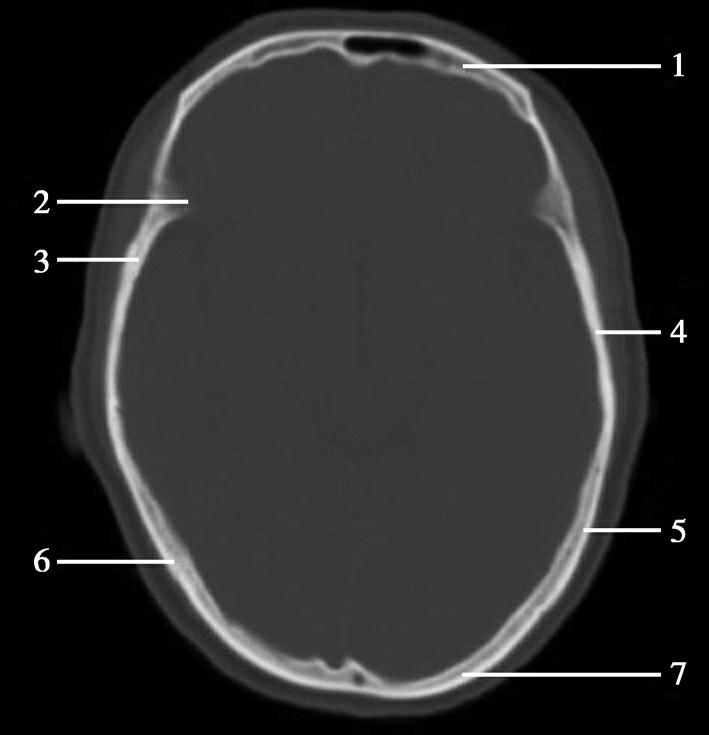

重要结构:卵圆孔、棘孔、破裂孔、斜坡、颞骨岩部、颈静脉孔(图1-2-1、图1-2-2)。

图1-2-1 颅底层面

A.横断面;B.横断面标注

1.晶状体;2.筛窦;3.颞肌;4.中颅窝底;5.外耳道;6.延髓;7.乙状窦;8.小脑半球;9.眼球;10.眼眶;11.上颌窦;12.蝶窦;13.乳突;14.耳郭;15.小脑蚓部;16.枕内隆凸